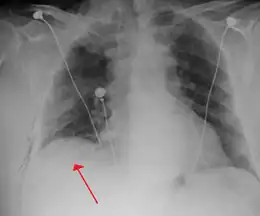

Chest X-ray

A plain chest radiograph, ideally with the X-ray beams being projected from the back (posteroanterior, or "PA"), and during maximal inspiration (holding one's breath), is the most appropriate first investigation.[32] It is not believed that routinely taking images during expiration would confer any benefit.[33] Still, they may be useful in the detection of a pneumothorax when clinical suspicion is high but yet an inspiratory radiograph appears normal.[34] Also, if the PA X-ray does not show a pneumothorax but there is a strong suspicion of one, lateral X-rays (with beams projecting from the side) may be performed, but this is not routine practice.[15][19]

Anteroposterior inspired X-ray, showing subtle left-sided pneumothorax caused by port insertion

Lateral inspired X-ray at the same time, more clearly showing the pneumothorax posteriorly in this case

Anteroposterior expired X-ray at the same time, more clearly showing the pneumothorax in this case

Chest X-ray showing a pneumothorax on the right (left in the image), where the absence of lung markings indicates that there is free air inside the chest

Chest X-ray showing the features of pneumothorax on the left side of the person (right in image)